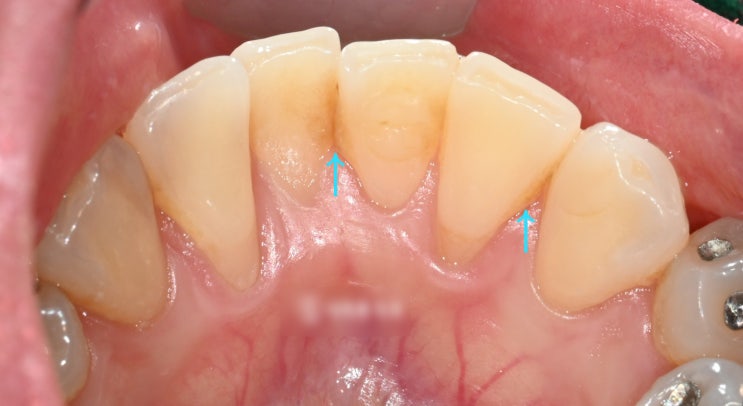

신촌역치과 정기검진의 중요성 다수의 충치 재발, 인레이, 신경치료

안녕하십니까, 대표원장 조민기입니다. 여러분들께서는 정기검진 을 받으신지 얼마나 되셨나요? 많은 분들...